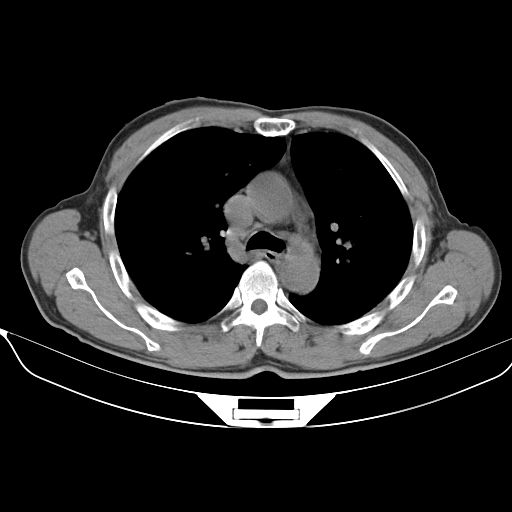

以下是引用心路寻觅在2010-3-1 10:23:00的发言:[br]1、考虑左肺上叶周围型肺癌[br]2、右上肺陈旧性病灶。[br][br][本贴已被 心路寻觅 于 2010-3-1 10:40:18 修改过]

以下是引用shuiyuan在2010-3-1 10:45:00的发言:[br]考虑左肺上叶中心型肺癌伴阻塞型炎症,邻近胸膜受侵。